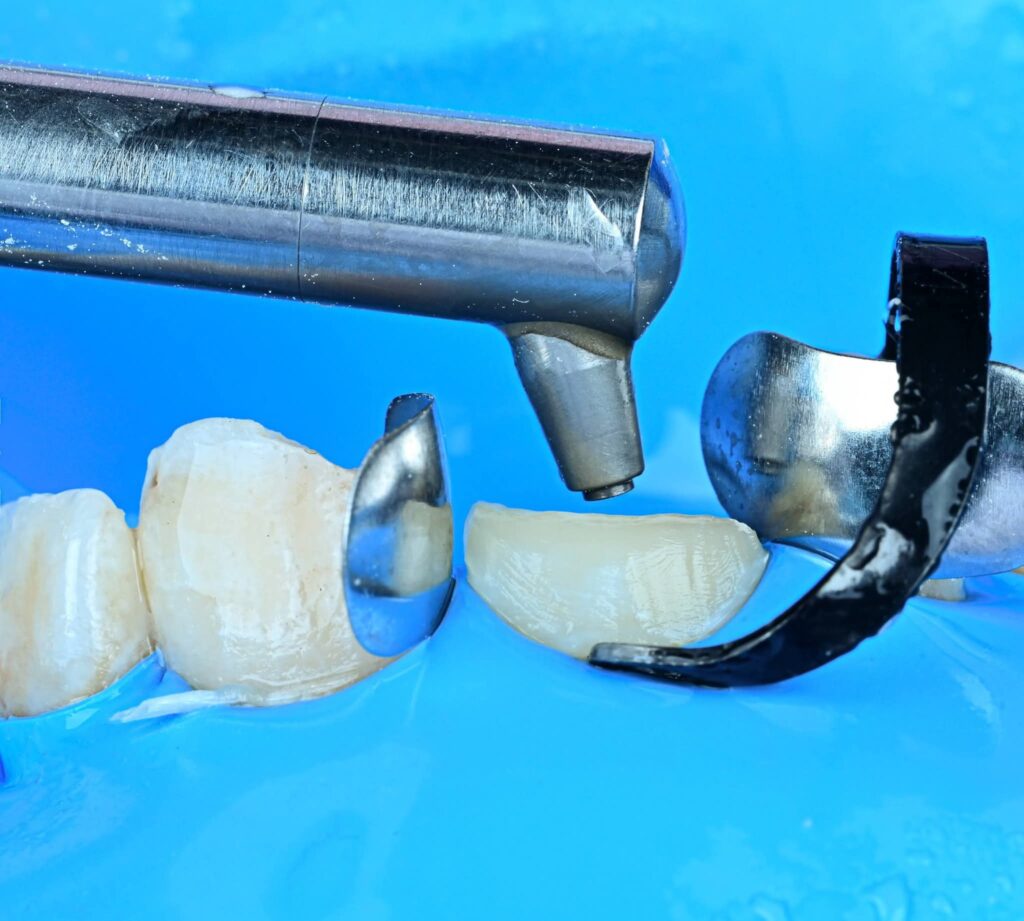

Symmetry and proportionality are fundamental principles in aesthetic dentistry, particularly in direct composite veneers, where the clinician acts simultaneously as a scientist and an artist. Successful veneers are not determined only by color and shape, but by the harmony between teeth, gingiva, lips, and face.

From an artistic perspective, the clinician should consider:

Progressive embrasure increase from central to canine

2. Line angle positioning to control perceived tooth width

3. Surface texture and light reflection